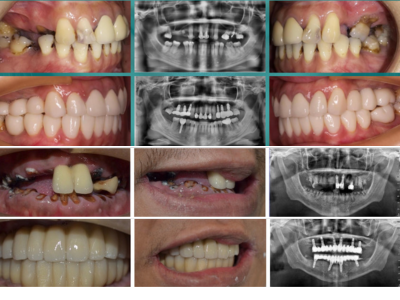

專業醫師,守護你的笑容 我們結合國際級植牙系統與數位美學技術,提供無痛、精準、快速的牙科治療體驗。從植牙、全瓷冠到隱形矯正,一次滿足你的需求。 預約諮詢 關於我們 精準重建每一個笑容 陳俊岳醫師率領的專業團隊,結合國際植牙技術與數位牙科系統,專精於微創植牙、全口重建、全瓷冠與隱形矯正。我們相信醫療不只是技術的展現,更是傾聽與信任的累積,讓每位患者都能安心重拾自然笑容。 醫師介紹 你所需要的牙科服務,一次到位 從植牙、全瓷美學到隱形矯正,為你提供最適合的解決方案 All-on-4 全口重建 透過四支植體即可支撐全口固定假牙,手術當天即可恢復咀嚼與笑容。省時、安全,是全口重建的高效新選擇。 微創植牙 結合 3D 導引技術與數位影像分析,僅需微小切口即可完成植牙。傷口小、恢復快,是患者首選的無痛精準植牙方式。 全瓷貼片 / 全瓷冠 高透光全瓷材質,重現自然笑容。從牙齒美白、縫隙修飾到整體微笑設計,打造專屬自信風采。 隱形矯正 透明舒適、可自行摘戴,結合數位3D掃描與模擬,讓矯正過程幾乎隱形,同時維持生活自信與美觀。 服務項目 想擁有更自信的笑容我們幫你實現! 不論是植牙、貼片還是矯正, 專業醫師團隊都會為你量身打造最自然的治療方案。 一次預約,即可完成影像健檢與療程規劃。立即體驗數位牙科的高效與舒適。 預約諮詢 選擇我們 精準醫療 × 美學設計 × 人本關懷 專業與溫度兼具的牙科團隊 陳俊岳醫師帶領的團隊結合國際植牙系統、數位牙科技術與多年的臨床經驗,為每位患者量身打造最適合的治療方案。我們堅持以人為本,讓治療更安全、美觀且長久穩定。 精準定位、傷口小、恢復快 客製化笑容美學設計 傾聽需求、尊重選擇,讓醫療更有溫度 診療案例 患者見證 他們的笑容,證明一切 「以前害怕看牙,來這裡完全改觀。醫師很有耐心,手法也很細膩, 植牙後完全沒有不適,現在咬東西都很自然。」 陳小姐・植牙治療 「我做了全瓷貼片,笑起來真的差好多! 醫師幫我設計的牙齒形狀超自然,朋友都以為是我原本的牙齒。」 林小姐・全瓷貼片美學修復 「我選擇做 All-on-4 全口重建,手術當天就能吃東西, 整個過程比想像中輕鬆很多,非常感謝團隊專業又溫柔的照顧。」 黃先生・全口重建 立即撥打 02-25533202 台北市大同區承德路二段176號 (捷運民權西路站2分鐘) 官方Line預約諮詢 台北院所 預約專線 02-25533202 台北市大同區承德路二段176號 (捷運民權西路站2分鐘) 台南院所 預約專線 06-3117111 台南市永康區中華二路189號 官方Line預約諮詢